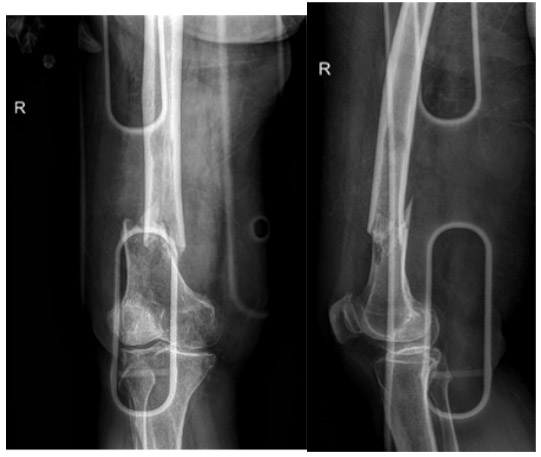

Before the surgery: X-ray shows a lytic lesion and displaced fracture in the distal end of the right femur.